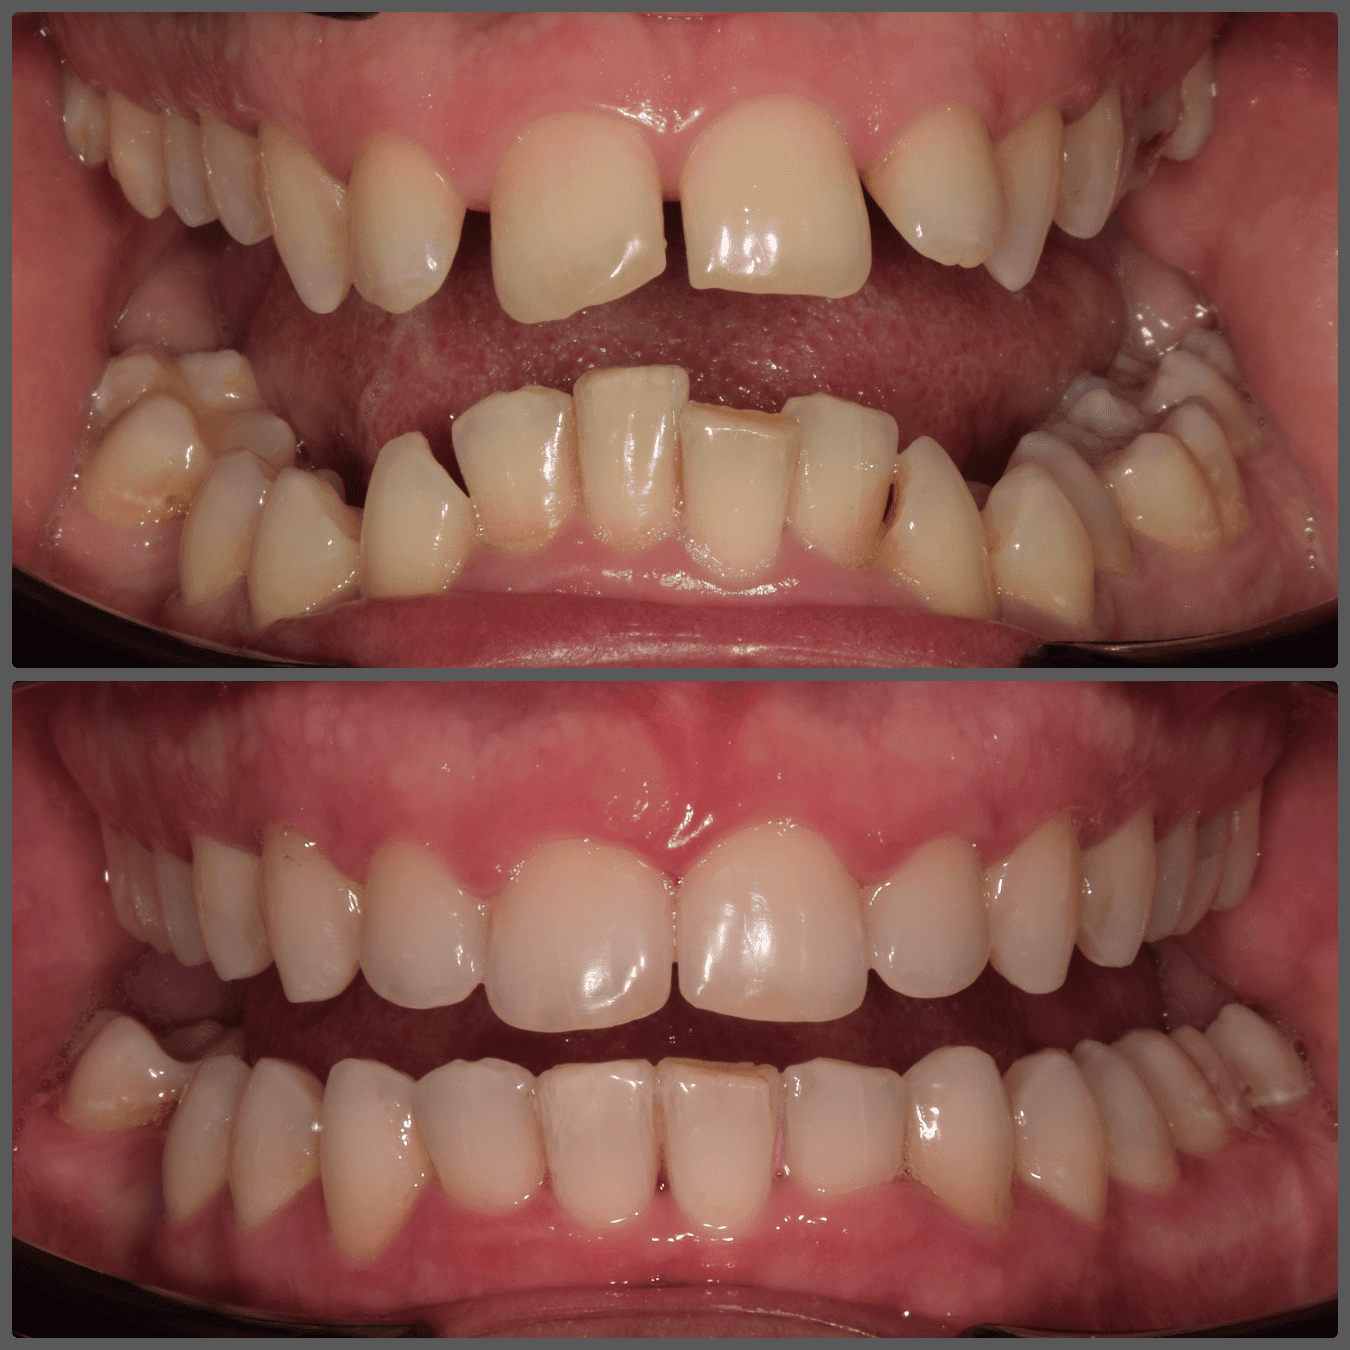

Balázs súlyos alsó torlódása miatt keresett fel magánrendelésemen. A diagnosztikus vizsgálatok során előbbin túl alsó-felső fogívszűkületet, valamint nyitott harapási hajlamot állapítottam meg. Kezelését Pitts21 alsó-felső rögzített fogszabályozó készülékkel kezdtük meg. A nyitott harapási hajlamot a hátsó fogakra helyezett harapásemelővel kontrolláltuk. A torlódott fogaknak tolórugóval és interproximális redukcióval teremtettünk helyet, és intermaxilláris gumihúzással tökéletesítettük a harapást. A fogszabályzó kezelés teljes időtartama alatt Balázs 110%-osan együttműködő volt, ezért 21 hónap alatt sikerült kiemelkedő végeredményt elérnünk.